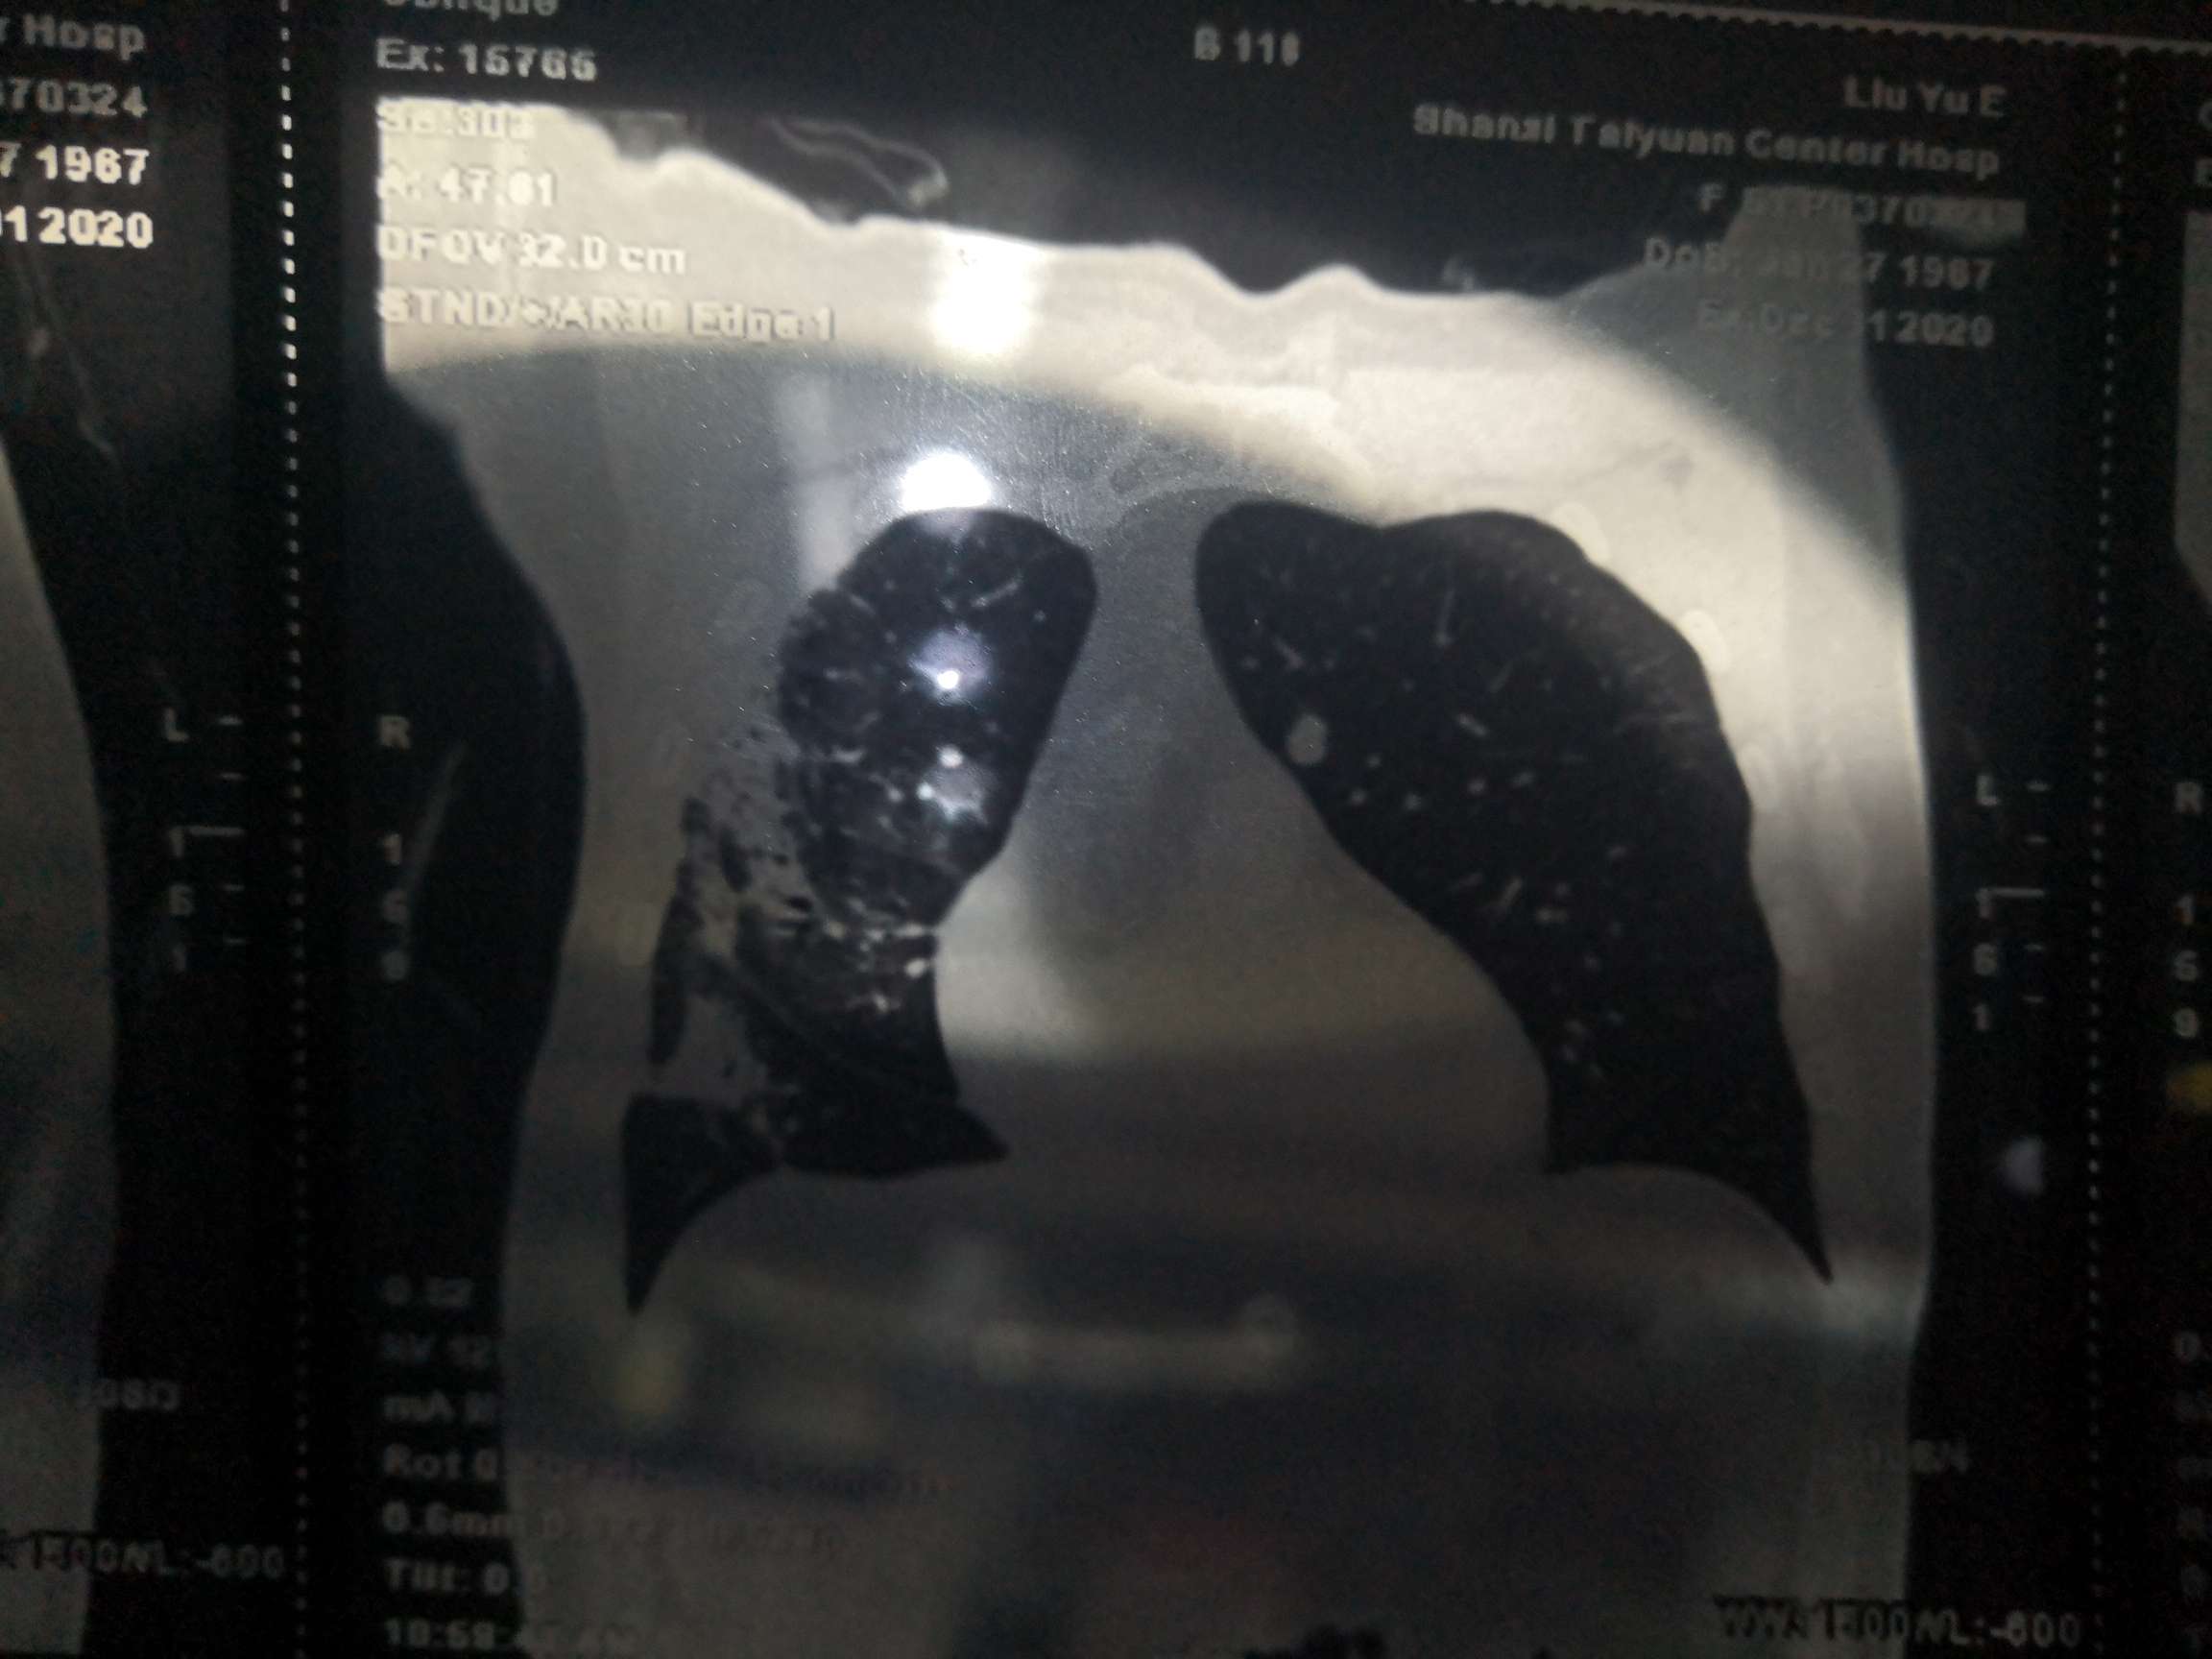

姜教授:肺部小结节包括磨玻璃样改变、混合磨玻璃改变、实性结节,也有微小结节、小结节和结节之分。各种肺部病变有不同的鉴别诊断方法,临床处理和共识完全不一样。良恶性的判断需要结合影像学诊断、穿刺、活检。

姜教授:依据结节的性状,如果这是纯的磨玻璃结节,看结节大小、CT值、边界情况来决定。初次发现结节,不管是什么结节,不管磨玻璃还是混合型磨玻璃、还是实性结节,初次发现之后都应先做随访。不是发现小结节立马就要手术,所有医生和患者都要牢牢记住这个共识。